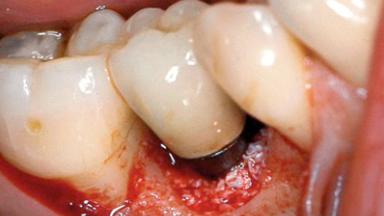

Excess Cement Resulting in Peri-implant Infection Presenting as a Draining Sinus Tract

Biological complications caused by undetected cement residue have been receiving much attention. Excess cement might be responsible not only for rapidly developing of peri-implantitis, but also for delayed or chronic manifestations of the disease many years after cementation (Wilson 2009; Linkevicius and coworkers 2013). Invitro and clinical studies have shown that it is very difficult or even impossible to completely clean up excess cement at subgingival margins, so popular in cemented restorations (Agar and coworkers 1997; Linkevicius and coworkers 2011, 2012). Possible outcomes of biological complications due to excess cement range from temporary inflammation of the peri-implant soft tissues without any serious esthetic and functional consequences all the way to implant loss. This report describes a case of peri-implantitis caused by residual cement; as well as the management and quite unusual resolution of the complication. The patient presented in 2009 with a draining sinus tract, tenderness on chewing, and tissue contact above the implant-supported restoration. The implant had been restored approximately three years before.